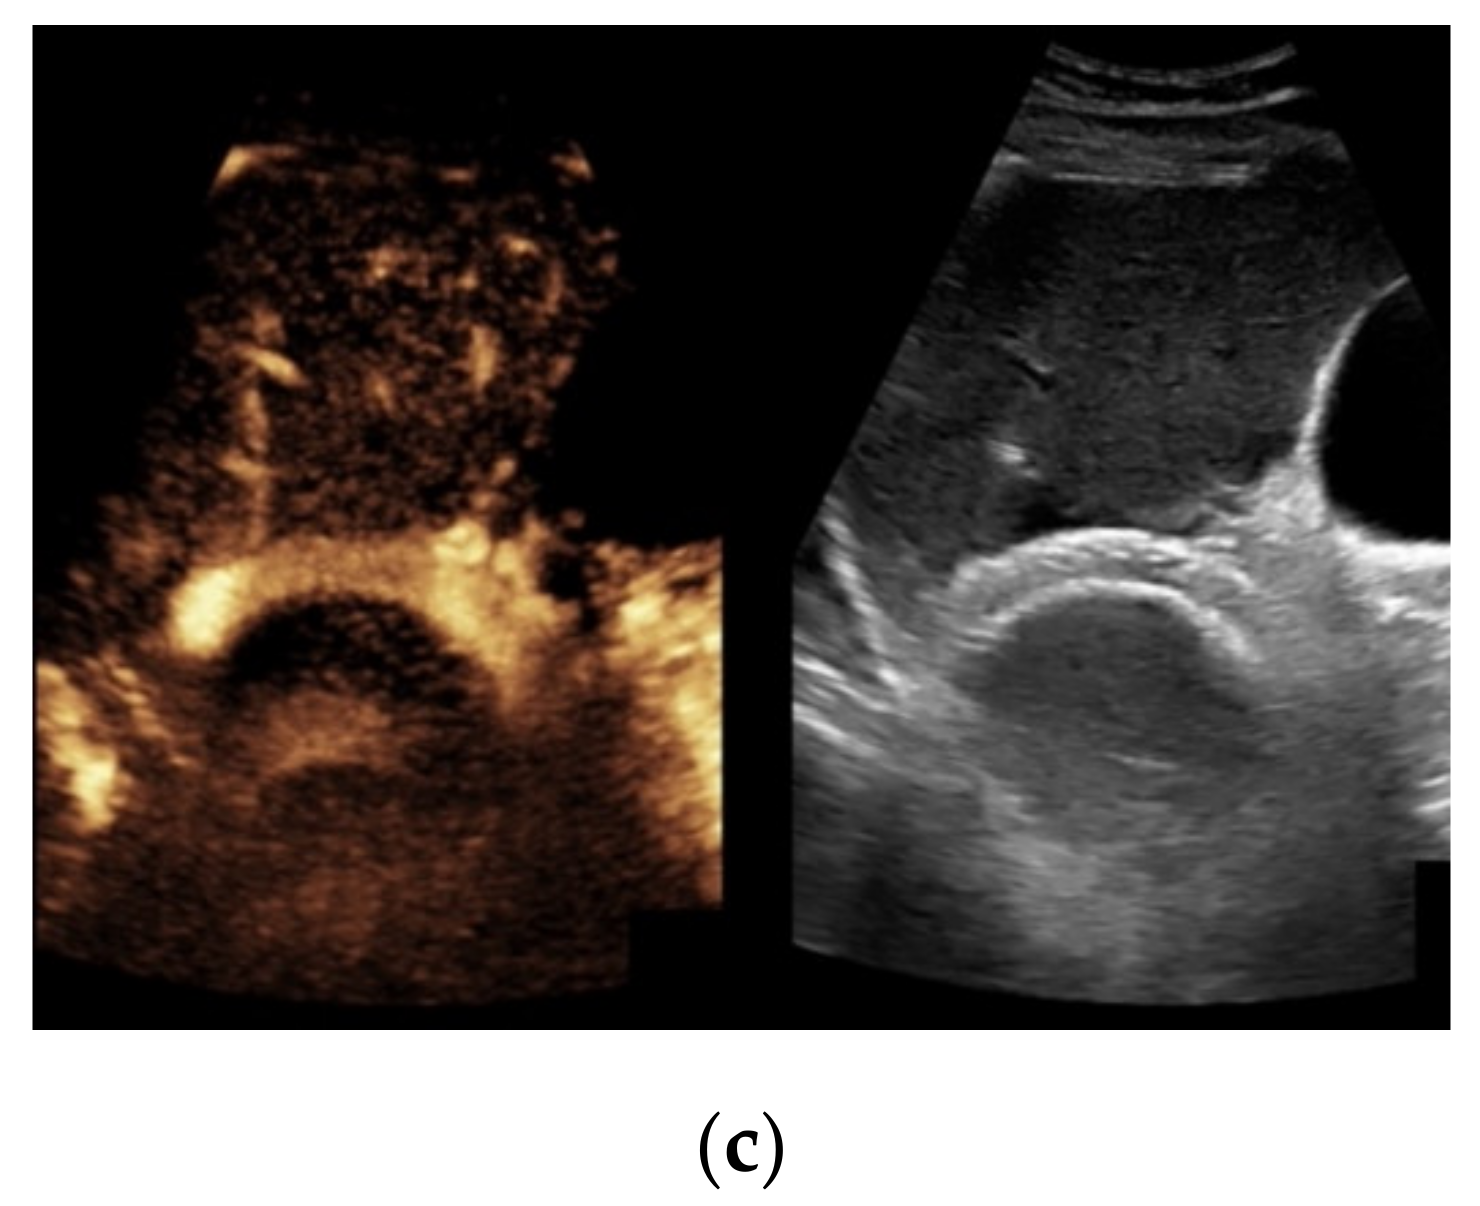

Figure 4. Same patient as in Figure 1 with continuous flow within the transjugular intrahepatic portosystemic shunt (TIPS) without thrombosis or occlusion using microflow imaging (a) and after administration of contrast agent (b,c).